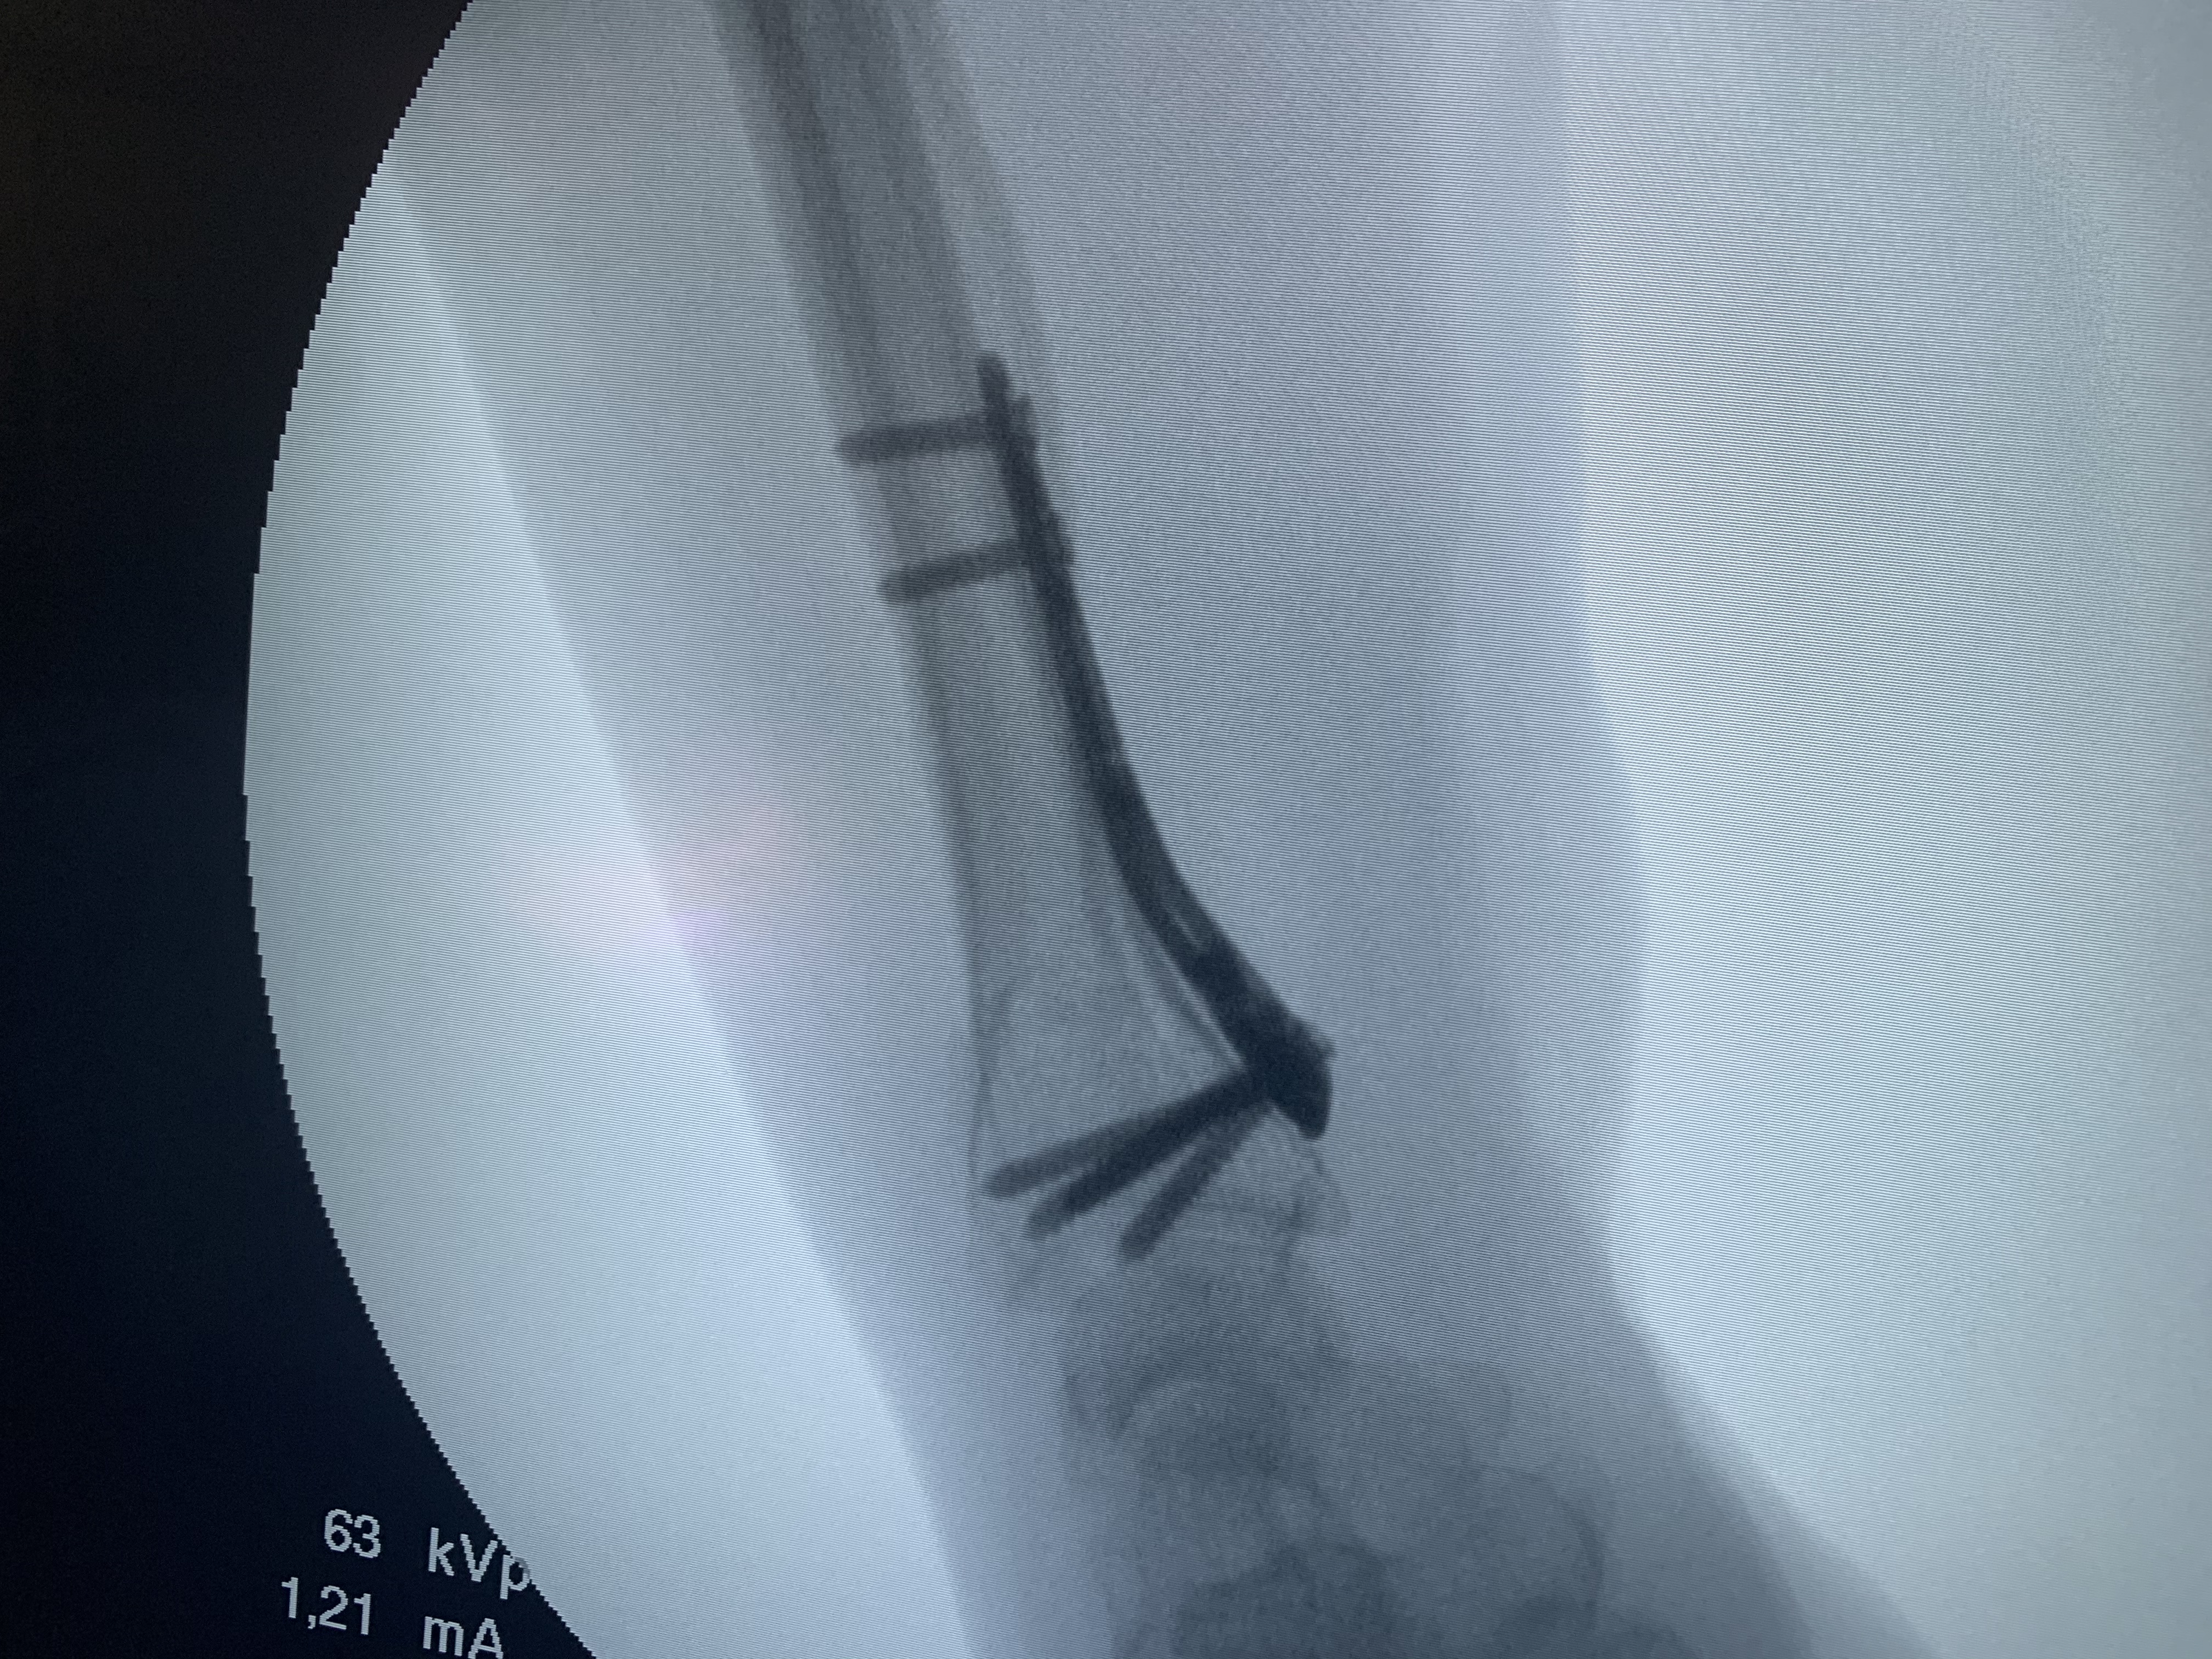

Galería de fotos clínica, servicios, cirugías, casos de pacientes Visítenos, ambiente limpio, agradable y seguro. Trabajando Operando en tiempos de coronavirus Dr Barquero Traumatologo Compartir en X (Se abre en una ventana nueva) X Comparte en Facebook (Se abre en una ventana nueva) Facebook Imprimir (Se abre en una ventana nueva) Imprimir Compartir en WhatsApp (Se abre en una ventana nueva) WhatsApp Enviar un enlace a un amigo por correo electrónico (Se abre en una ventana nueva) Correo electrónico Me gusta Cargando...